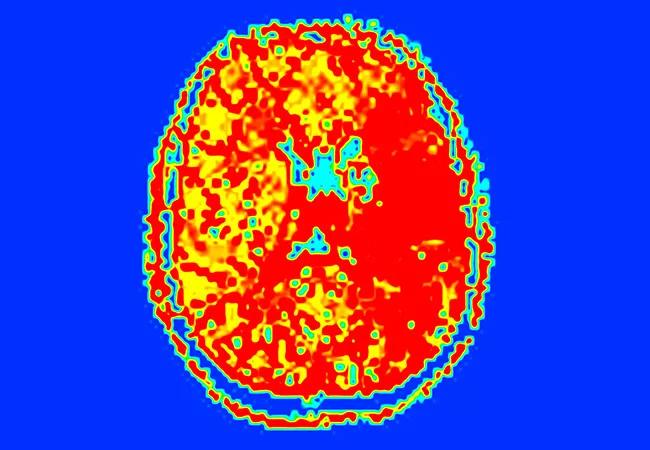

He was listed for heart transplantation, but before a match was found he developed an acute left hemispheric syndrome with sudden-onset unresponsiveness and a dense right hemiplegia. His NIH Stroke Scale (NIHSS) score was 23. Brain MRI and MR angiogram showed an acute deep infarct involving the left basal ganglia and corona radiata (Figure 1) secondary to a left M1 middle cerebral artery occlusion, with a large perfusion deficit involving much of the left hemisphere (Figure 2).

Figure 1 (left). Diffusion-weighted image showing the patient’s acute left basal ganglia and corona radiata infarct. Figure 2 (right). Perfusion image showing a deficit involving much of the left hemisphere.